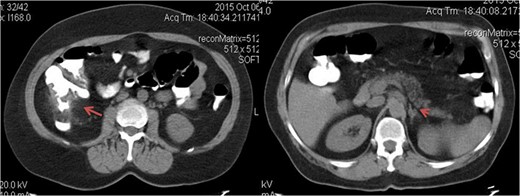

A 63-year-old female patient, with no medical history of relevance, presented with a palpable mass in the right flank which she first noticed a month ago, associated with chronic anemia. After performing a computed tomography (CT) scan, a circumferential thickening of the cecum and the ascending colon walls and a slight enlargement of the left adrenal gland (20 × 15 mm2 in diameter) were observed (Fig. 1). There was no evidence of liver or lung metastases. At the time of diagnosis, the serum carcinoembryonic antigen (CEA) level was 0.6 ng/ml.

Axial tomographic view with oral contrast. The red arrow shows the tumor in the right colon and the arrowhead pointing synchronous contralateral adrenal metastasis.